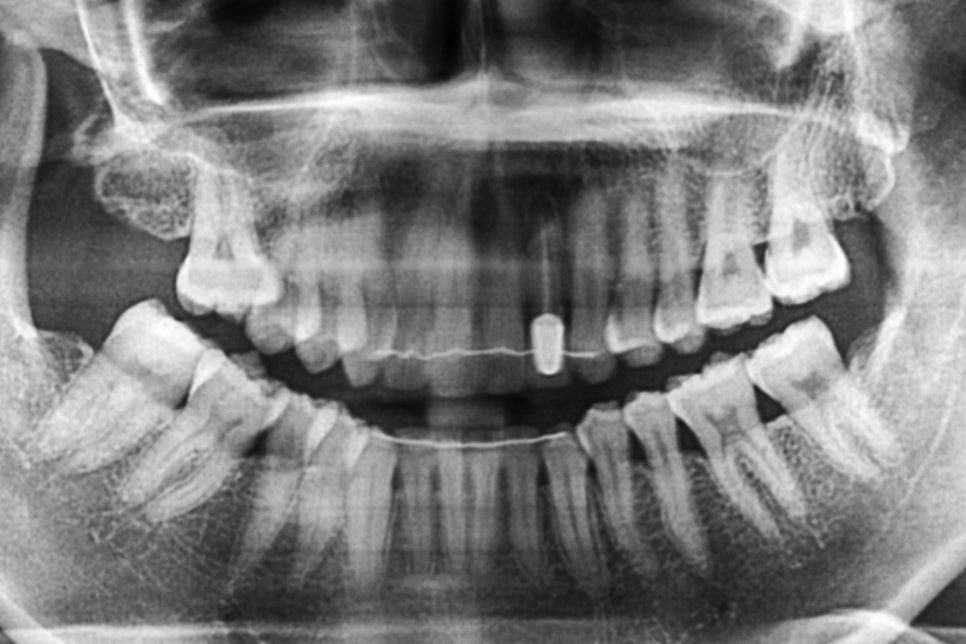

신논현역치과 교정 전 파노라마 엑스레이 사진을 보시면

상악 측절치의 치근과 형태를 확인할 수 있습니다.

확실히 주변 치아와 비교하여 치근이 짧고

뒤틀림이 심한 모습인데요,

이렇게 맹출된 부분이 지나치게 작거나

짧은 경우 치아의 함입을 의심해 볼 수 있습니다.